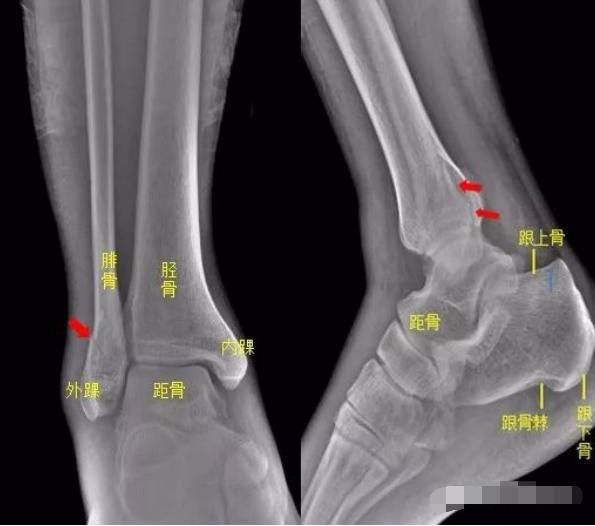

踝关节

患者右踝关节被电动车砸伤,拍片如下:

所示右侧腓骨远端见斜行骨折线,骨折端对位对线尚可,右腓骨远端骨折。